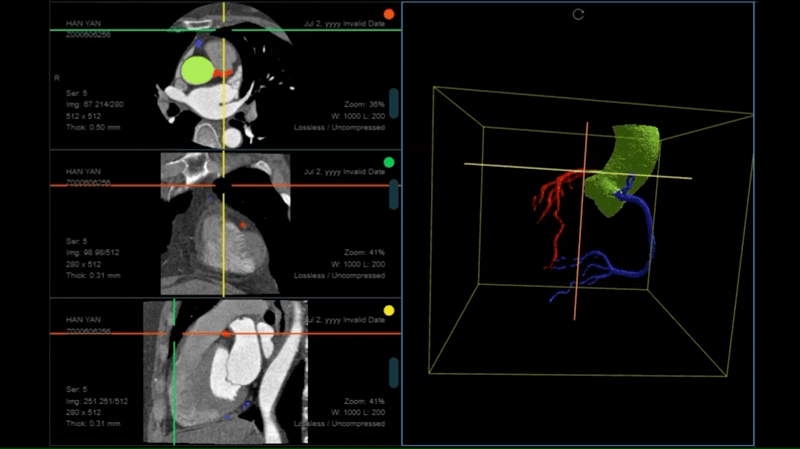

多人、多团队、多中心医学影像云原生协同标注与高级可视化平台。通过医学影像分割大模型及多种AI技术,灵活支撑不同规模的数据标注团队高效完成医学影像协同标注工作,支持自动标注、半自动标注、手工标注、三维标注、形态学测量,提高放射学影像的标注效率和质量。

业内领先的医学影像标注平台,以基于Web云原生的模式,通过医学影像分割大模型及多种AI技术,灵活支撑不同规模的数据标注团队高效完成医学影像标注工作。提供基于医学影像分割大模型MISM、以及深度学习、机器学习自动化标注工具,自动分割医学影像中的器官、病灶与组织,为医学研究提供金标准数据,提高手术规划的效率。

提供医疗影像数据标注和共享平台,支持医疗机构之间的数据共享与协作,开展多中心的临床科研与临床试验,以及多团队协同开展疾病诊断、治疗方案制定与手术规划。